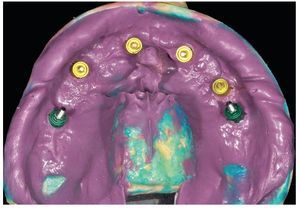

Tras una fase de curación sin complicaciones, se esperaron otros dos meses antes de ajustar las prótesis provisionales a las condiciones ahora estables de la mucosa. Se rebasaron los espacios intermedios formados a causa de la detumescencia del tejido blando tras la intervención, a fin de reducir o incrementar el volumen del cuerpo de la prótesis conforme a las indicaciones funcionales, higiénicas, fonéticas y estéticas, así como teniendo permanentemente en cuenta la oclusión. Una vez concluida esta fase pueden tomarse las impresiones para la restauración definitiva (figs. 75 a 79). Para la restauración de puente planificada, se toman las impresiones a nivel del implante.

Fig. 76. La toma de impresión definitiva en el maxilar superior tiene lugar a la altura del hombro del implante.

Fig. 77. La toma de impresión definitiva en el maxilar inferior tiene lugar a la altura del hombro del implante.

Fig. 78. Vista detallada de la impresión del maxilar superior.

Fig. 79. Vista detallada de la impresión del maxilar inferior.